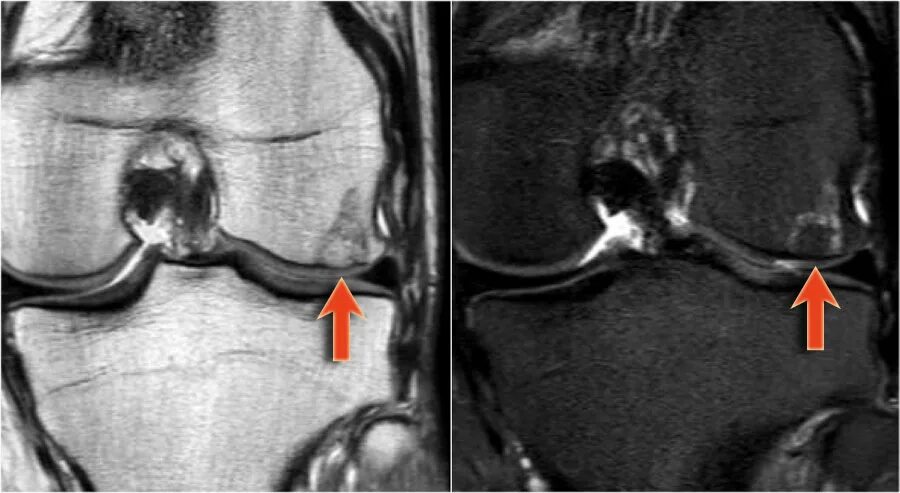

Повреждение хряща по outerbridge